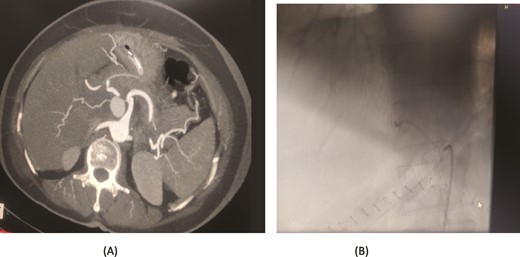

A 56-year-old female underwent a pancreaticoduodenectomy (PD) for pancreatic head adenocarcinoma. On the 6th postoperative day, she presented with nausea and vomiting. A contrast-enhanced CT scan revealed the presence of a pseudoaneurysm originating from the common hepatic artery. Angioembolization was promptly performed to control the bleeding. The procedure was successful, and the patient recovered well postoperatively. At follow-up, the patient was doing fine with no further complications (Fig. 2).

Case 2. (A) CT angiogram showing pseudoaneurysm CHA. (B) Angioembolization of CHA with gel foam